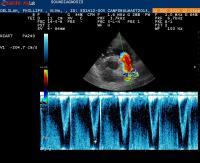

Significance of low fractional shortening for pulmonic stenosis?